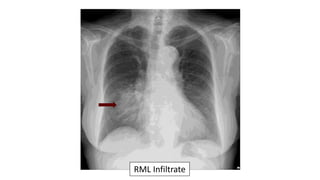

57 year old with cough

and shortness of

breath.

The CXR demonstrates:

a. Pulmonary edema

b. RLL pneumonia

c. RML pneumonia

d. Pulmonary embolus

e. Lung cancer

RML pneumonia:

ď‚§ Blurred right heart border

ď‚§ Lateral diaphragm clear

ď‚§ Often seen best on the lateral

RML Infiltrate

• Right middle lobe pneumonia